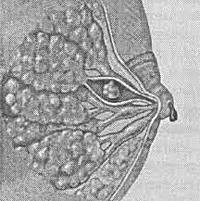

Макроскопически внутрипротоковая папиллома молочной железы напоминает кистозное образование с сосчковидными разрастаниями. Папилломы легко травмируются, а выделяющаяся при этом кровянистая жидкость попадает в выводные протоки и выделяется наружу из соска. В области опухоли возможны кровоизлияния и некрозы; озлокачествлению чаще подвергаются множественные внутрипротоковые папилломы молочной железы.

Интрадуктальные папилломы могут быть одиночными (солитарными) и множественными; их размеры варьируют от нескольких миллиметров до 1-2 см в диаметре. Солитарные папиллярные опухоли чаще локализуется в субареолярной области; множественные - ближе к периферии железы.